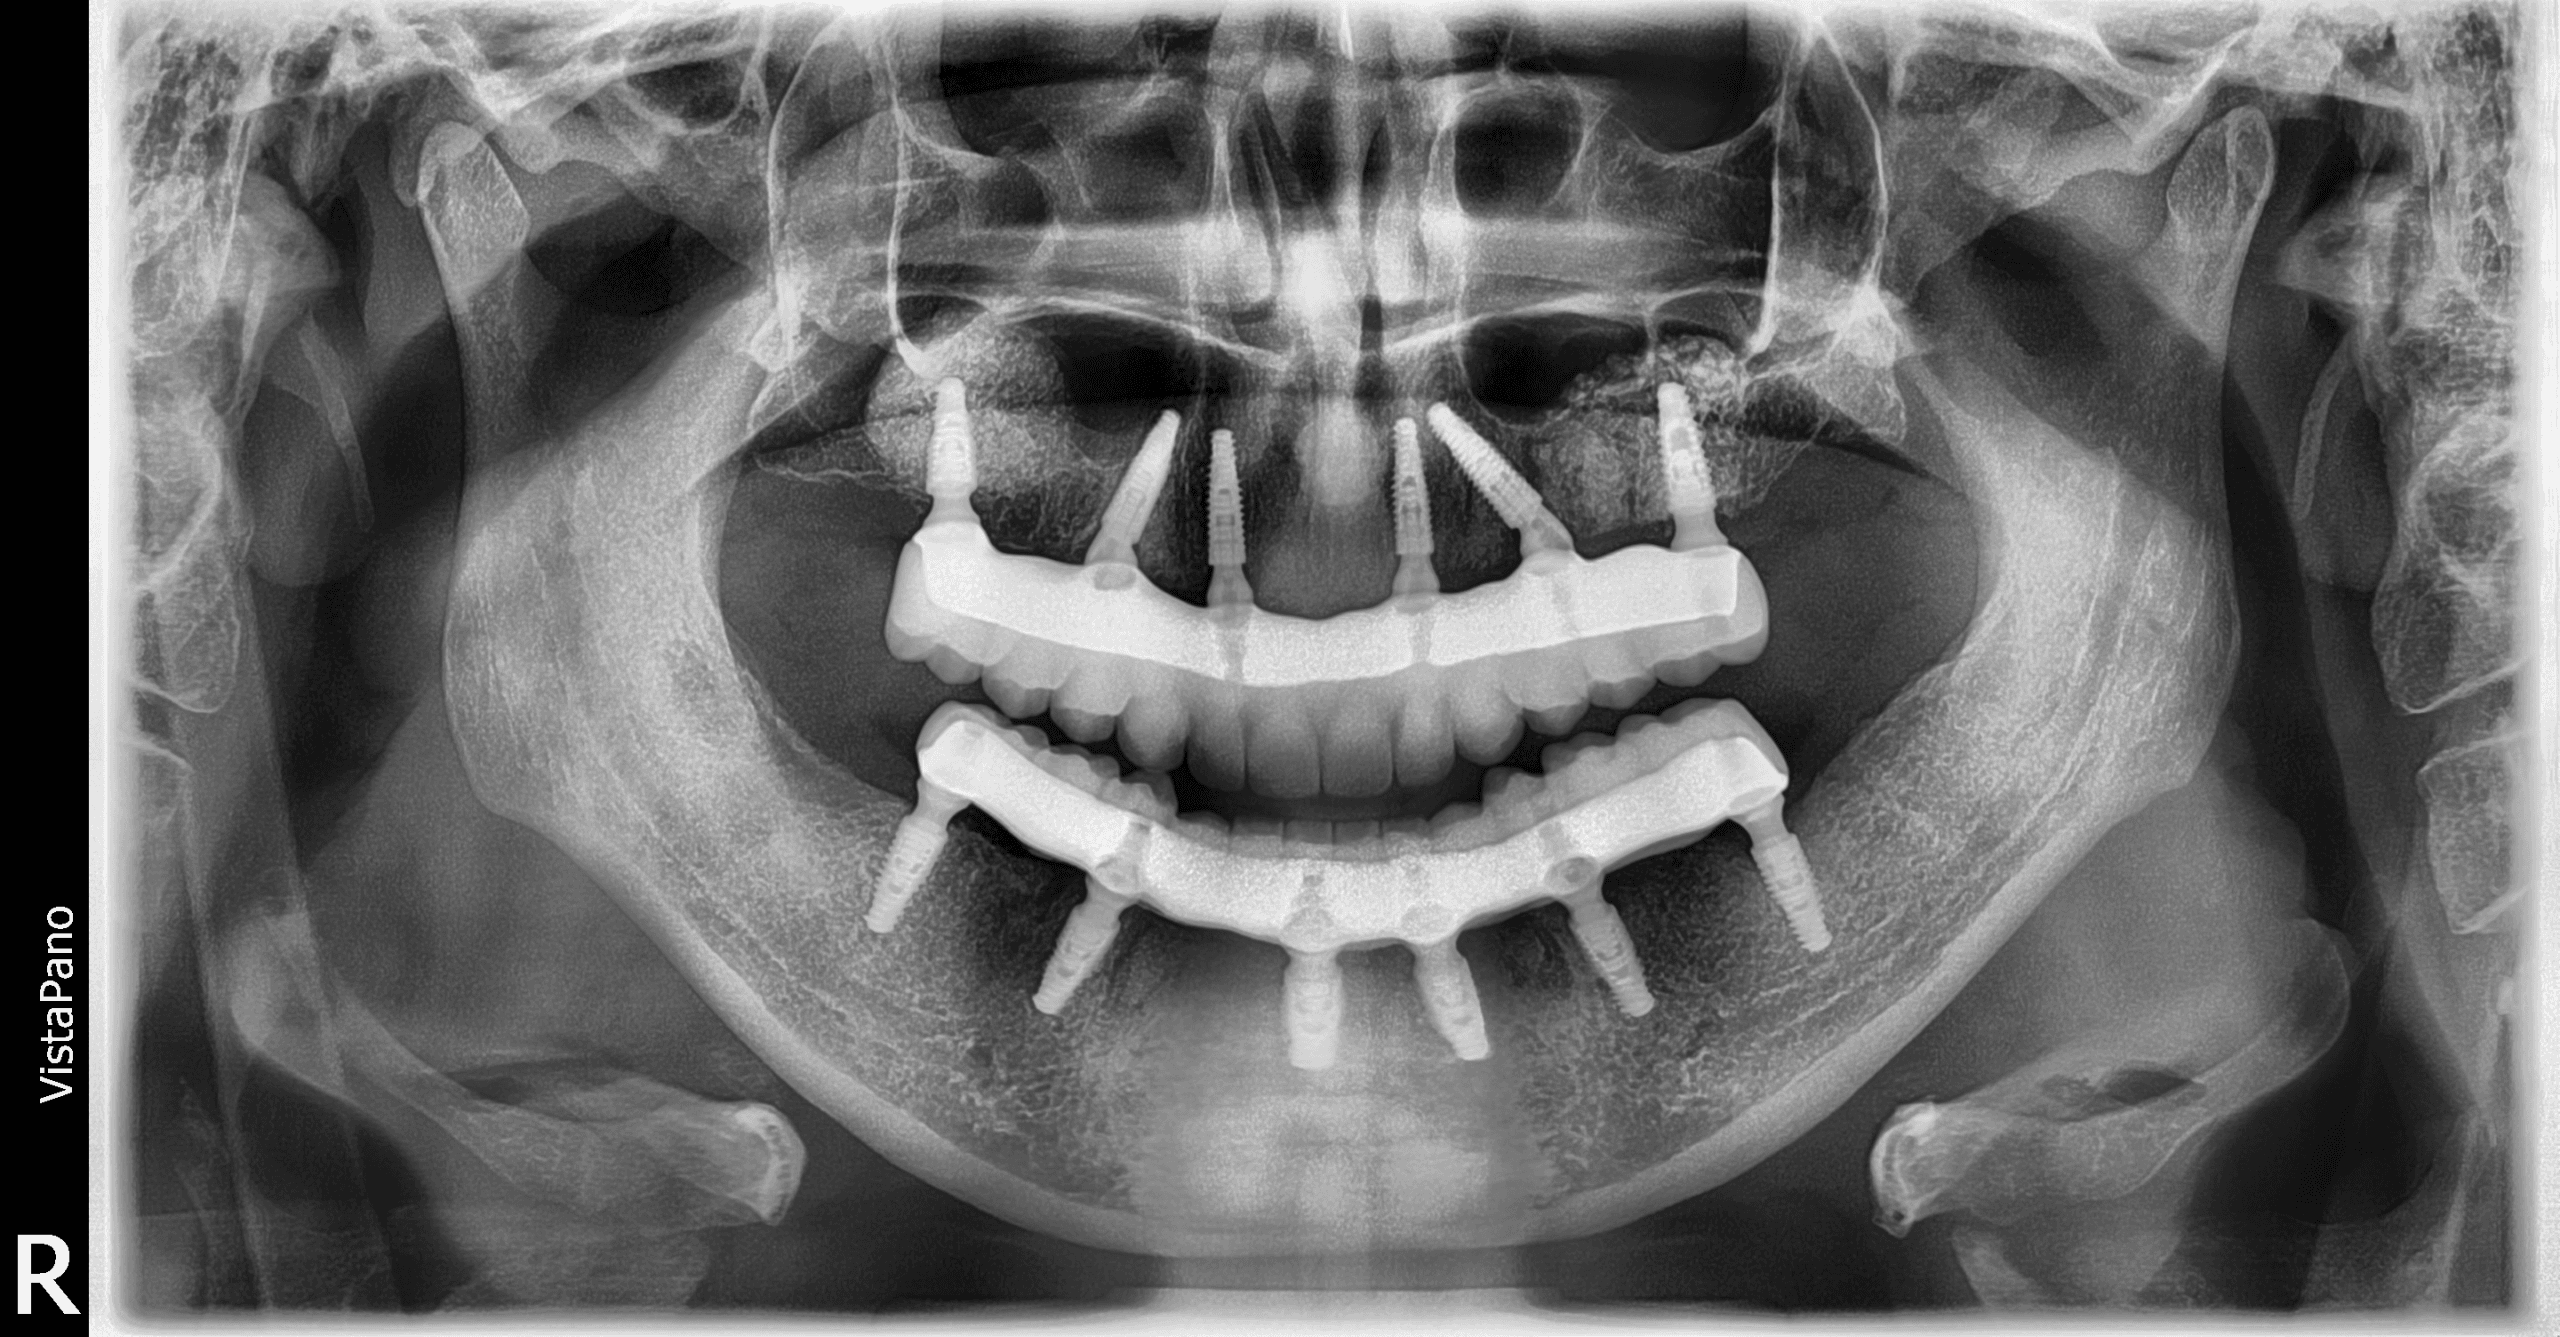

Sistemele All-on-4 și All-on-6 reprezintă cea mai modernă metodă de reabilitare completă a danturii. Cu ajutorul a 4 sau 6 implanturi dentare, poți avea o lucrare fixă, care arată și funcționează ca dinții naturali.

Redarea funcției masticatorii și estetice prin restaurări complexe cu ajutorul coroanelor pe implanturi tip FP1, cu aspect natural si sănătos al gingiei.

Cu ajutorul investigației CBCT și scanării intraorale, simulăm poziția exactă a implanturilor înainte de intervenție. Astfel, inserarea este precisă și predictibilă.

Realizăm o radiografie panoramică și scanare digitală 3D pentru a evalua volumul osos și a stabili dacă All-on-4 sau All-on-6 este soluția ideală pentru tine.

Folosim analiza CBCT și scanarea intraorală pentru a vizualiza structura osoasă și a planifica poziția precisă a implantului. În acest scop, utilizam ghidurile chirurgicale in timpul celor mai multe intervenții.